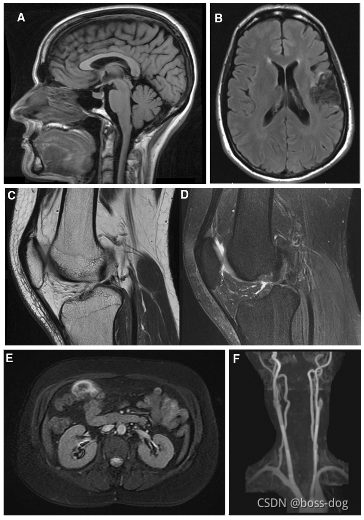

Magnetic Resonance Imaging (MRI,磁共振成像)

磁共振对软组织看的更清楚些。

磁共振可以把软骨看得很清楚。